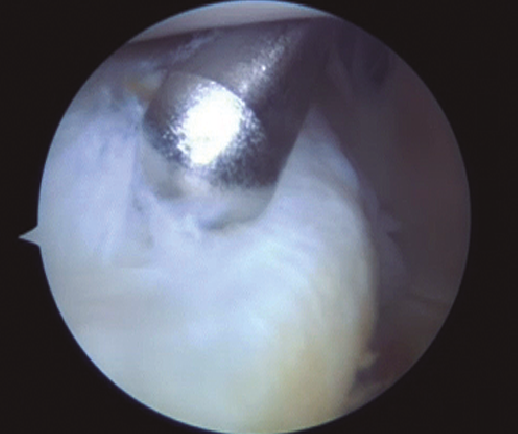

Se realiza una incisión con un bisturí del 11 bajo control artroscópico, realizando disección roma para crear el portal. En este momento podemos realizar la sutura “todo-dentro”. Primero se desbrida la lesión, regularizando los bordes con un sinoviotomo.

Figura 3. Visión a través del intercóndilo del desbridamiento de la lesión al nivel de la rampa posterior mediante sinoviotomo por el portal posteromedial.

Para la rodilla derecha usamos un gancho de curva izquierda y viceversa (Figura 3). Se introduce un pasasuturas de 25° de angulación (SutureLasso®, Arthrex) cargado con una sutura no reabsorbible del n.º 1 (PDS®, Ethicon, Inc., Somerville, NJ) por el portal PM. El pasasuturas se maneja de forma que la punta penetre la zona periférica del muro del menisco medial de fuera hacia dentro. Posteriormente, se introduce por la zona central del menisco. El extremo libre de la sutura se recupera a través del portal PM. Se realiza un nudo deslizante que se aplica a la zona posterior del menisco con un empujanudos y posteriormente se corta. Esta maniobra se repite en función de las necesidades del tipo de lesión meniscal, realizando una sutura cada 5 mm para lesiones limitadas al segmento posterior. Se debe prestar atención para no enredar las suturas entre sí.